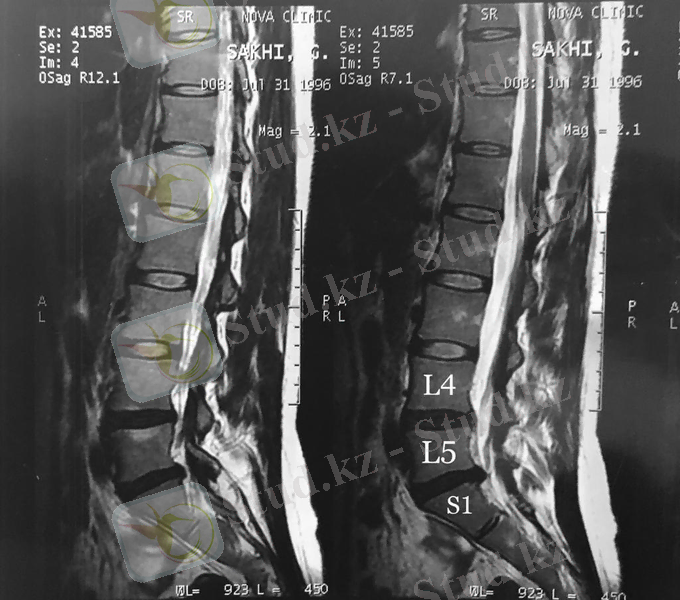

4-сурет. L4-L5 дискілерінің протрузиясы-3, 6 мм және L5-S1 дискілерінің жарығы-6 мм.

Менің жағдайымда бел ауруы бірнеше жыл бұрын пайда болды, бірақ қозғалыс, жүріс-тұрысқа айтарлықтай кедергі келтірмегеннен кейін бұған аса мән берілмеді. 2021 жылдың ақпан айында кенеттен аяғымды басып, жүре алмай қалу себебінен дәрігердің көмегіне жүгіндім. Маған «белдегі омыртқааралық дискілерінің және басқа да бөлімдерінің зақымдануы мен радикулопатия» деген диагноз қойылды. Яғни, L4-L5 диск бөлімдерінің протрузиясы 3, 6 мм, L5-S1 диск бөлімдерінің жарығы (грыжа) және радикулопатия ( жұлын жүйке тамырларының дисктегі жарық әсерінен қысылуы) .